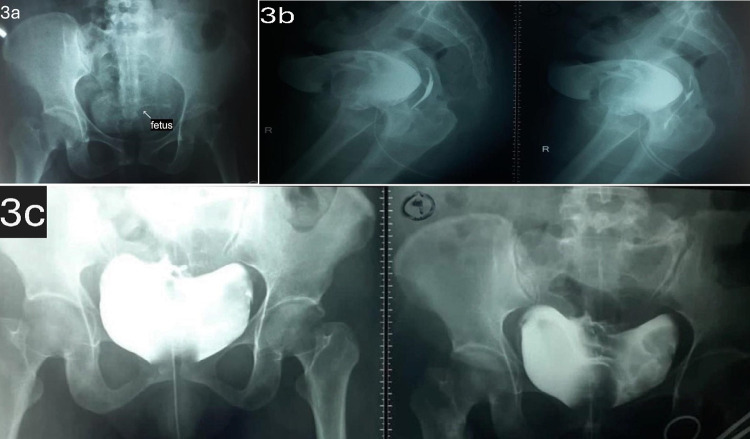

Vesicouterine fistula (VUF) is a rare form of urogenital fistula, accounting for approximately 4% of cases. It commonly arises as a complication of uterine interventions, especially previous cesarean sections (C-sections). Intravesical ectopic pregnancy complications are infrequent. We discuss a 39-year-old female with severe lower abdominal pain spreading to the flank, dysuria, hematuria, and urinary hesitancy one week after laparotomy for fetal demise at 17-18 weeks of gestation. A dead fetus in the urinary bladder along with the VUF was revealed in the imaging. The surgical operation identified a fistula between the posterior bladder wall and the lower uterine segment. Fetus evacuation and fistula repair were performed with symptom resolution achieved. A literature review was conducted and nine articles were extracted. These articles discussed the risk factors and complications of VUF. The articles, selected for relevance and quality, highlighted cesarean sections as the most common risk factor, with hematuria being the most frequent complication. Only a small number of cases had fetal migration into the bladder documented, showcasing its rarity. This case represents a rare complication of VUF: intravesical ectopic pregnancy into the bladder. Surgical intervention led to favorable outcomes and is consistent with findings in the reviewed literature. The rare complication of VUF such as intravesical ectopic pregnancy requires proper diagnosis and treatment. This case emphasizes the importance of surgical management in achieving successful outcomes for VUF and its complications.